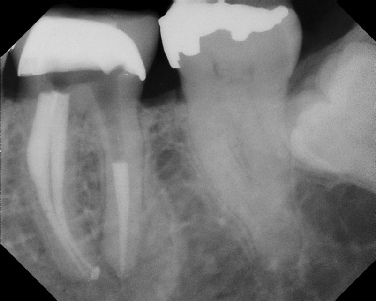

COMPLICATED ANATOMY LARGE LESIONS CALCIFIED CANALS PERFORATION / RESORPTION SEPARATED INSTRUMENTS SURGICAL CASES RETREATMENT / pOST REMOVAL OPEN APICES ACCESS THRU CROWNS Root Canal Case Portfolio

Pre-op Post-op 1 Post-op 2